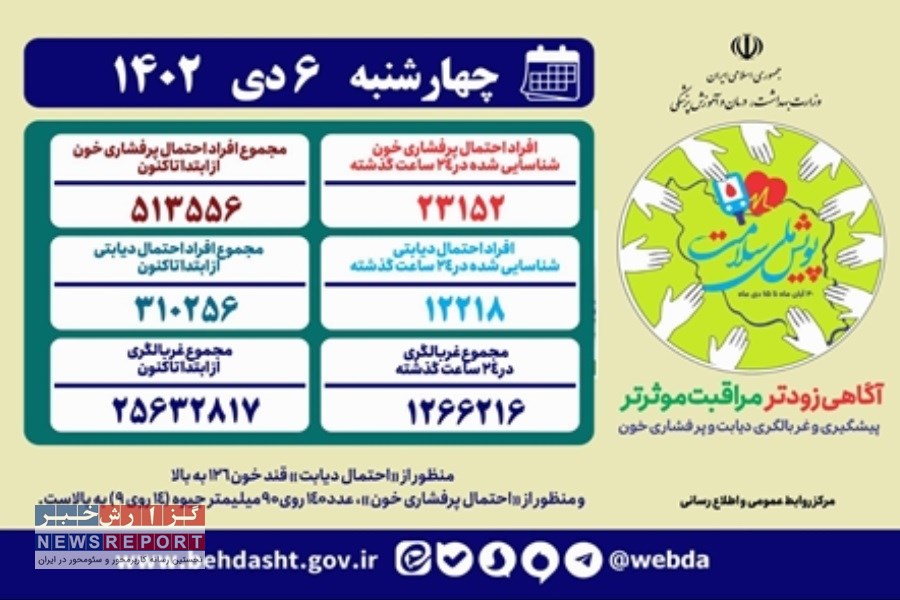

به گزارش خبرنگاران گروه جامعه گزارش خبر، از این تعداد ۵۱۳ هزار و ۵۵۶ نفر با احتمال ابتلا به پرفشاری خون و ۳۱۰ هزار و ۲۵۶ نفر با احتمال دیابت شناسایی شدند.

همچنین در ۲۴ ساعت گذشته یک میلیون و ۲۶۶ هزار و ۲۱۶ نفر در این پویش غربالگری شدند که از این تعداد ۲۳ هزار و ۱۵۲ نفر با احتمال پرفشاری خون و ۱۲ هزار و ۲۱۸ نفر با احتمال دیابت شناسایی شدند.

منظور از «احتمال دیابت» قند خون ۱۲۶ به بالا و منظور از «احتمال پرفشاری خون»، عدد ۱۴۰ روی ۹۰ میلیمتر جیوه (۱۴ روی ۹) به بالاست.